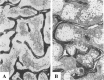

Marrow adipose tissue (MAT) is functionally distinct from both white and brown adipose tissue and can contribute to systemic and skeletal metabolism. MAT formation is a spatially and temporally defined developmental event, suggesting that MAT is an organ that serves important functions and, like other organs, can undergo pathologic change. The well-documented inverse relationship between MAT and bone mineral density has been interpreted to mean that MAT removal is a possible therapeutic target for osteoporosis. However, the bone and metabolic phenotypes of patients with lipodystrophy argues that retention of MAT may actually be beneficial in some circumstances. Furthermore, MAT may exist in two forms, regulated and constitutive, with divergent responses to hematopoietic and nutritional demands. In this review, we discuss the role of MAT in lipodystrophy, bone loss, and metabolism, and highlight our current understanding of this unique adipose tissue depot.